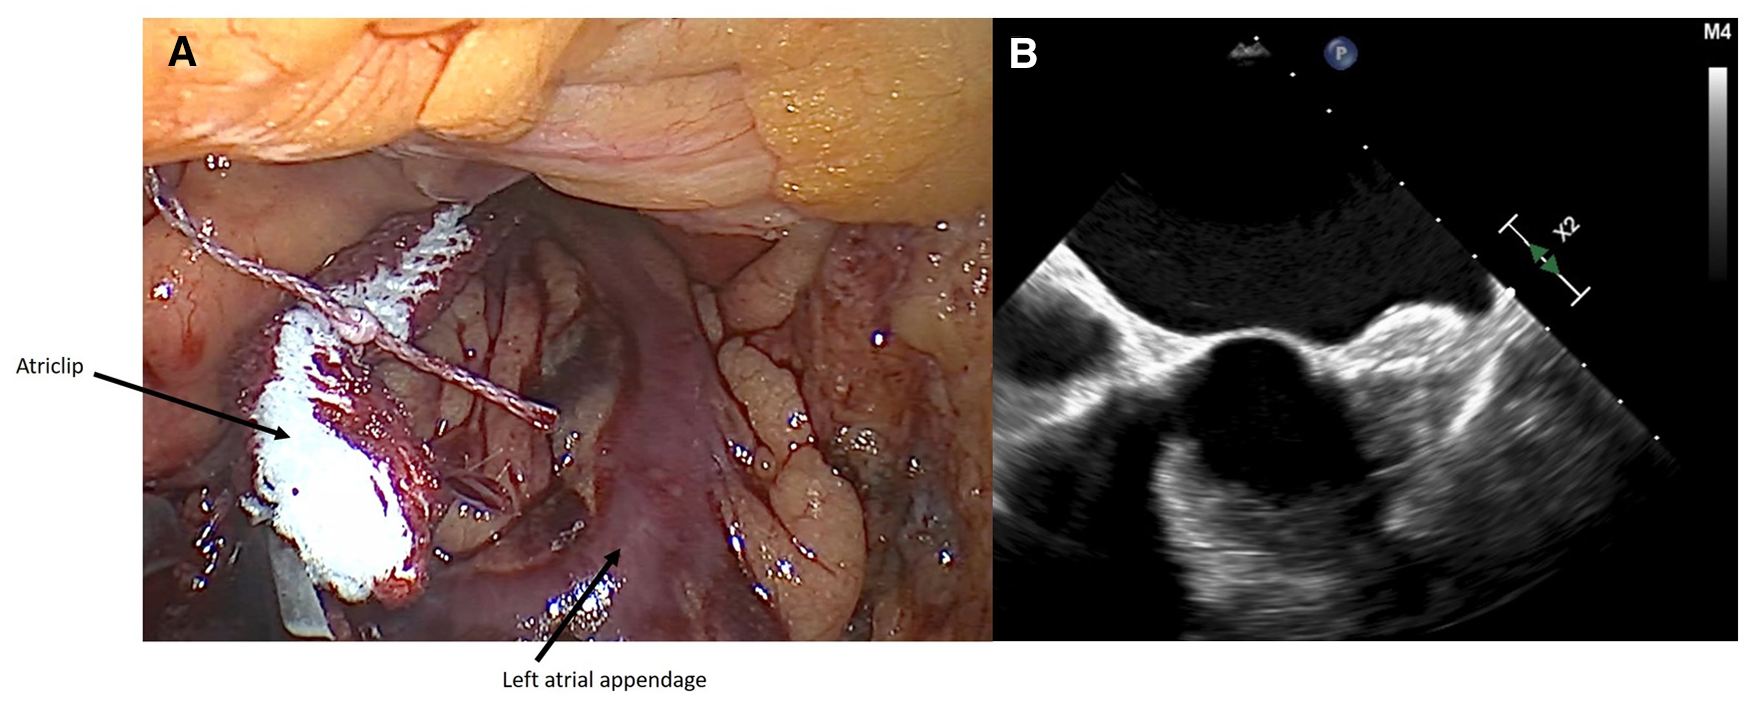

Figure 2

(A) intraoperative closure of LAA with AtriClip PRO2® device. (B) Intraoperative transesophageal echocardiography showing successful closure of LAA.